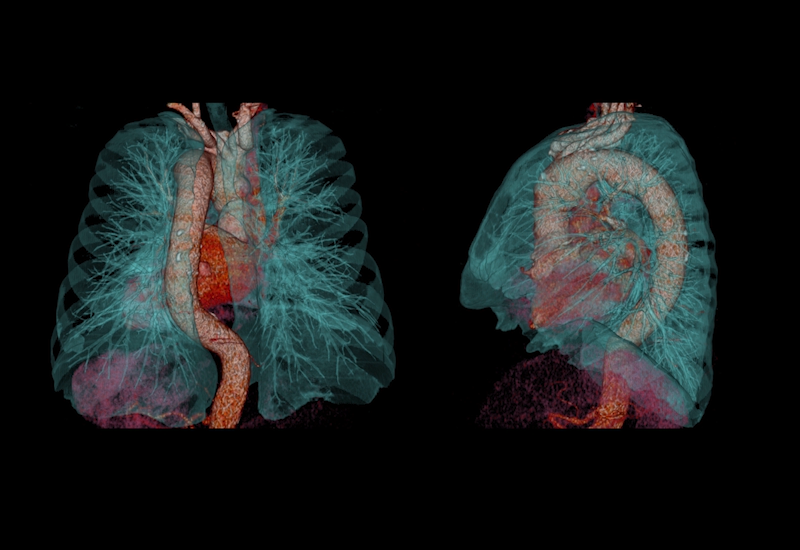

SURESubtraction Lung

Йодное картирование позволяет без проблем идентифицировать зоны недостаточного наполнения легких. Усовершенствованный алгоритм регистрации анатомических образований, настроенный на визуализацию паренхимы легкого.

Упрощенная генерация 3D изображений

Технологии Aquilion Lightning позволяют создавать объемные изображения с исключительной простотой. Одним нажатием кнопки осуществляется выбор необходимого протокола, что позволяет моментально вывести на экран нужные изображения.